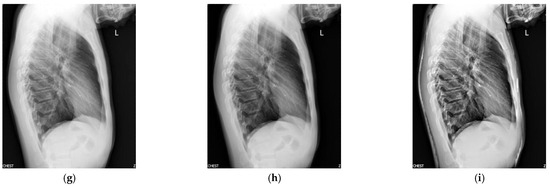

Figure 3 shows the enhancement images of eight approaches experimented on X-ray image 3. Figure 3a shows the original X-ray image 3; Figure 3b shows the enhancement result computed by McCann—the image is too bright, resulting in the loss of image details; Figure 3c shows the image achieved by RLBHE—the image is too dark, the useful information is lost; Figure 3d depicts the result achieved by RESIHE—the effect of enhancement is not obvious; Figure 3e shows the image obtained by TBCSSR—the image becomes gray and it is difficult to observe the details; the results enhanced by GDGIF, SMIPC, and FuzzyII are shown in Figure 3f–h, respectively. They are very similar and the enhancement effect is not prominent. Our method is depicted in Figure 3i—it performs well, and more details are retained. Table 3 shows the evaluation index values of the methods in Figure 3. Our method obtains the best values for all the metrics.

Figure 3.

Comparison on X-ray image 3. (a) Original image; (b) McCann; (c) RLBHE; (d) RESIHE; (e) TBCSSR; (f) GDGIF; (g) SMIPC; (h) FuzzyII; (i) Proposed method.